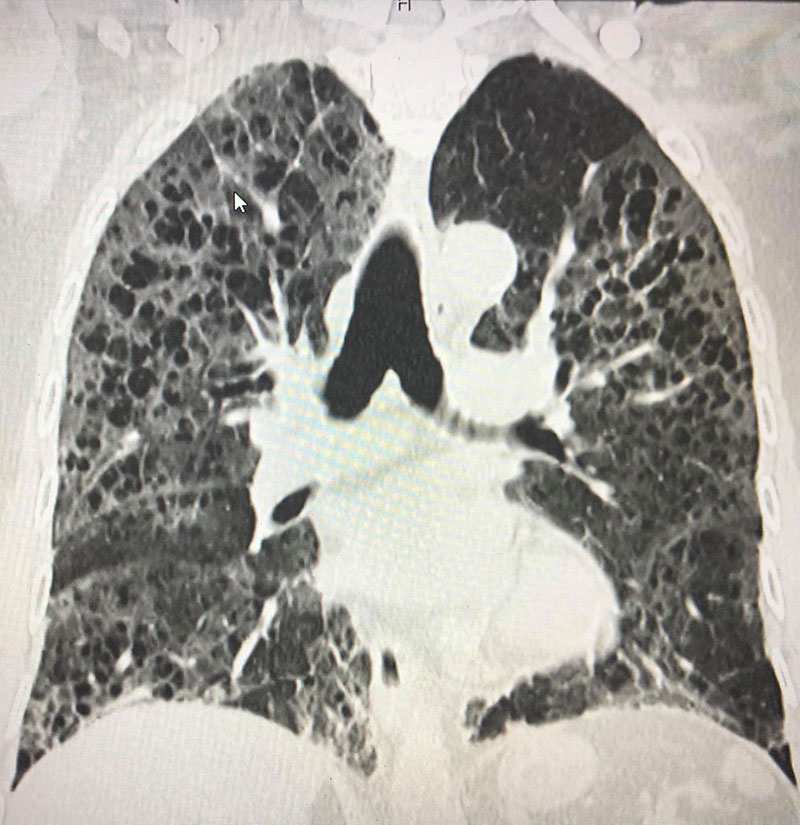

สำหรับเจ้าของปอดรายนี้ เป็นชายไทยวัย 80 ปี ไม่ดื่มเหล้า ไม่สูบบุหรี่ ติดเชื้อจากลูกหลานที่มาเยี่ยม เมื่อเอกซเรย์ปอดพบฝ้าขาว 2 ข้าง พอสแกนปอดพบเนื้อเยื่อปอดอักเสบรุนแรง มีทั้งฝ้าขาว รอยโรคเหมือนร่างแห และลักษณะผิดปกติคล้ายรังผึ้งกระจายทั่วไป